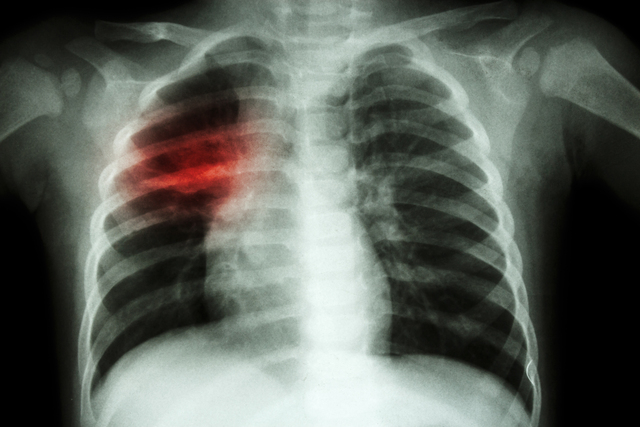

Sigara, tüm organlara ciddi derecede zarar verirken, özellikle akciğerler üzerinde ölümcül riskler oluşturabiliyor. Öyle ki akciğer kanserinin yüzde 90’ından sigara sorumlu oluyor. Prof. Dr. Bülent Tutluoğlu, sigaranın zararlarını şöyle sıraladı: